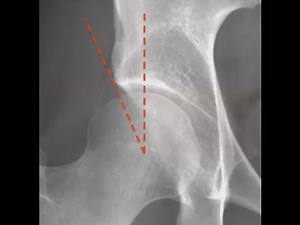

Center Edge Angle - Centers Edge

Roof Calculator - Acetabular

Angle - Biomechanics of Hip

Joint PDF - Acetabular Anteversion